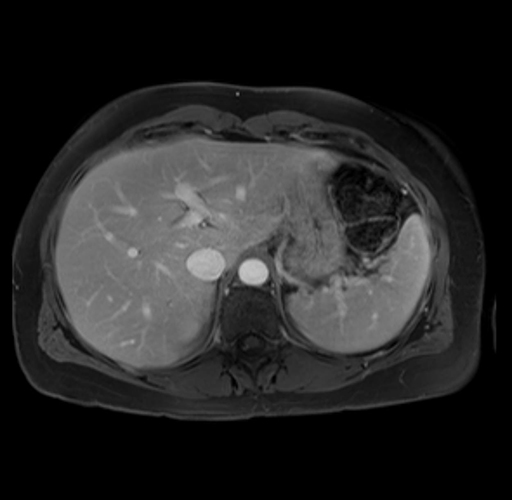

Imaging Analysis

Look through the patient's CT scan to identify any areas of concern for the necessary procedure.

Based on your CT findings, which issue(s) are present and would give reason for "planned slowing down moment(s)" in this case?

Considering a standard distal pancreatectomy procedure, what step(s) of the operation would you do differently in this case?